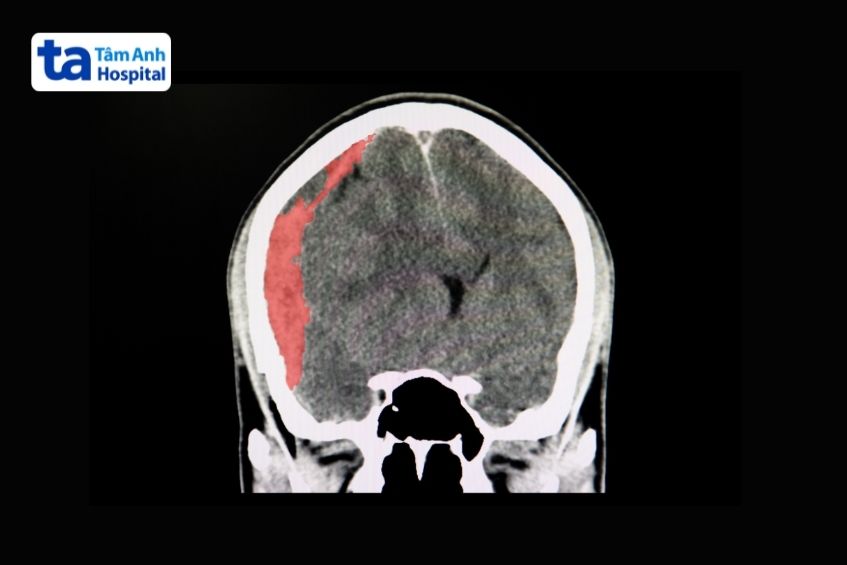

Tụ máu dưới màng cứng (subdural hematoma): Biểu hiện bằng hình liềm tăng tỷ trọng, mặt lồi bám vào xương sọ, mặt lõm hướng về mô não. Ban đầu, máu tụ dưới màng cứng cũng có tỷ trọng như máu tụ ngoài màng cứng. Theo thời gian, máu bị giáng hóa và hấp thụ, tạo thành vùng đồng tỷ trọng hoặc giảm tỷ trọng so với mô não, gọi là ổ tụ máu mãn tính. (1)

Ảnh chụp CT biểu hiện máu tụ dưới màng cứng